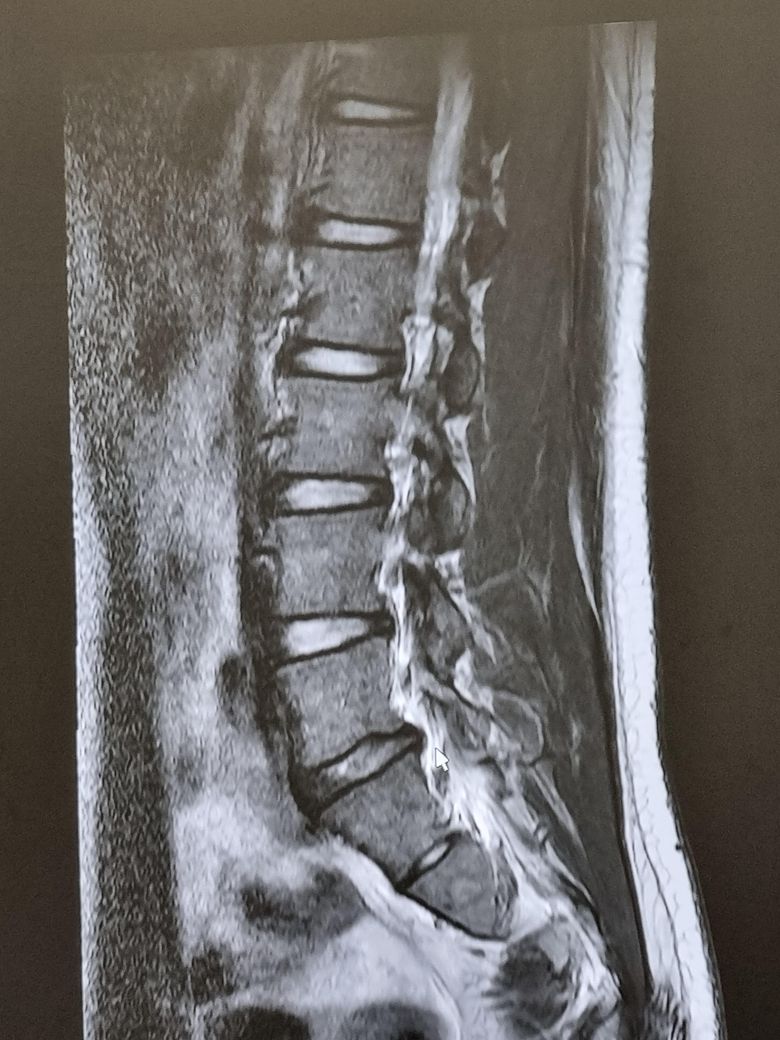

사진으로 디스크가 심한지 구분해주실분 구합니다.

다리 방사통이 있어서 병원에서 mri촬영을하고 염증 가라 앉하는 주사 맞고 계속 3개월간 주사치료해야한다는데 혹시 사진으로 보았을때 심한상태인가여 아니면 자연치유가 가능할까요 제발 알려주세요 부탁드립니다

MRI 사진을 보면 디스크가 신경을 누르고 있는 정도에 따라 심각도가 달라지며 이는 전문의의 정밀 판독이 필요합니다. 다리 방사통이 있다면 신경 압박은 확실한 상태로 보이고 주사치료나 물리치료로 호전될 수 있는 경우도 많아요 다만 증상이 심하거나 지속되낟면 수술적 치료까지 고려될 수 있으니 두세곳 병원에서 의견을 들어보는 것도 추천드립니다

4,5번 쪽에 디스크가 조금 튀어나온거 같은데, 제가 여러 환자들 본 경우 사진상으로는 그렇게 심해보이진 않습니다 재활 운동하고 잘하는 도수치료 받으시면서 디스크가 더 튀어나오지 않게 잘 관리 해주시면 정상 활동 가능합니다

심하지 않습니다 영상을 전반적으로 다시 봐야 정확한 설명이 되겠지만 우선 지금 보여주신것만 보면 가벼운 디스크 탈출입니다. 요추 5번/천추 1번 사이에 있습니다.

이런 경우에 요추전만 자세만 잘 하고있어도 자연적으로 회복이 됩니다. 방사통이 많이 불편하다면 주사치료를 해서 통증을 줄여놓고 허리를 절대 구부리지 않는 요추전만 자세만 해주시면 충분히 좋아지실 수 있겠습니다.